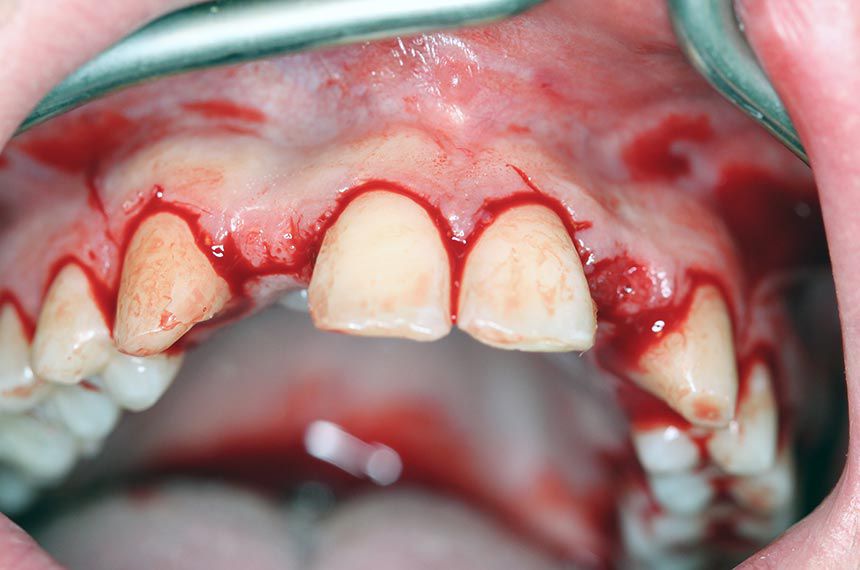

A marginal incision was made from the central incisor to the canine, including a releasing incision distally to avoid scar formation in the esthetic zone (Fig. 6). The mucoperiosteum was reflected (Figs. 7 – 8), and Straumann® BLT implants (Roxolid®, SLActive® 3.3mm/12mm) were placed in regions 12 (Figs. 9 – 11) and 22. The buccal bone was intact but needed horizontal augmentation to ensure long-term stability of the implant and to avoid grey shine through the gingiva and gingival recession. botiss cerabone® was added on the buccal side and covered with a botiss Jason® membrane. Emdogain® was added on top for better wound healing, and also because of its antibacterial activity (tooth position 12: (Figs. 12 – 14), tooth position 22: (Figs. 15 – 17). The periosteum was cut to obtain a tension-free primary closure (Figs. 18 – 19). Healing post-surgery was uneventful and, after 10 days, reached the status shown in (Figs. 20 – 21). The implants healed for three months before healing abutment surgery. The Maryland bridges were re-cemented in the meantime.